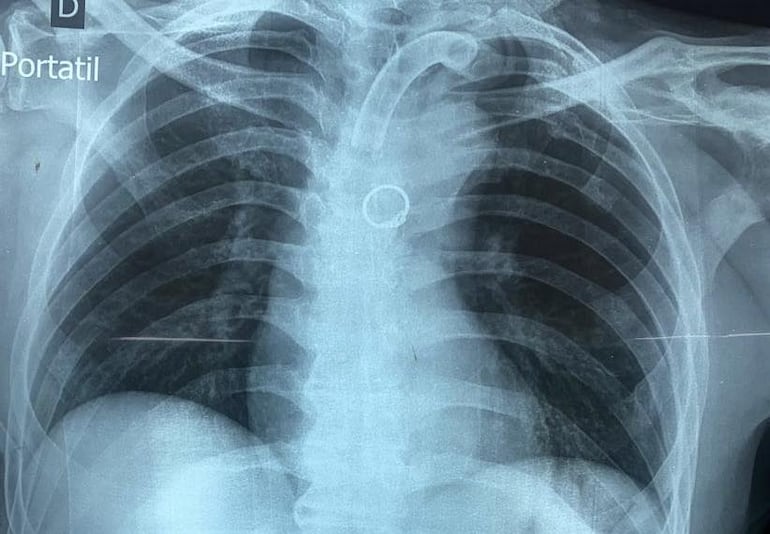

Como parte del protocolo, se le practicó una radiografía de control. Fue entonces cuando apareció una imagen extraña: una figura circular en el bronquio fuente izquierdo.

Lo que inicialmente parecía un error técnico o un “artefacto” en la imagen, terminó confirmándose mediante tomografía: se trataba de un objeto real.

El hallazgo: un anillo de oro en el bronquio

El neumólogo Carlos Morinigo relató el caso, señalando que el equipo médico se encontró con “lo impensado”: un anillo de oro de tamaño considerable alojado en el pulmón.